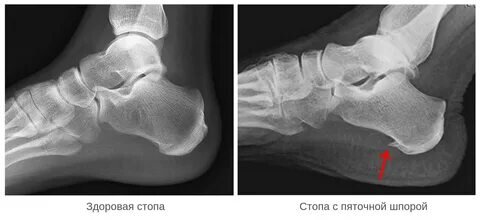

Дело в том, что около 30% людей имеют дополнительное костное образование на бугре пяточной кости, напоминающее шпору. Именно этому остеофиту(экзостозу) часто приписывают все симптомы плантарного фасциита, однако эти вещи практически никак не связаны, так как шпора может быть, а фасциита нет и наоборот.

Рентген практически бесполезен, может показать наличие шпоры, а может и нет, это сути не меняет, как мы уже говорили ранее. На МРТ и УЗИ можно увидеть воспаление или утолщение подошвенной фасции, что свидетельствует о плантарном фасциите, но бывает и при отсутствии симптомов.